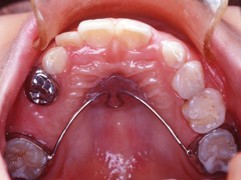

在混合齒列期中,維持將來永久牙長出時所需要的空間,也是乳牙存在的重要性之一。不幸的是,往往有許多的原因使得乳牙提早脫落,造成乳牙維持空間的功用消失。而使乳牙提早脫落的原因通常有:因為蛀牙太大,導致乳牙需要被拔除;因為意外創傷而使乳牙提早脫落;因為永久牙太大或異位生長而造成旁邊乳牙提早脫落;治療失敗的乳牙,需要提早被拔除…等等。

一旦乳牙提早不存在時,我們若沒有及時做好適當處理的話,這些寶貴的空間就會因後牙的前傾移動,而造成萌牙空間的消失;於是將來小孩齒列提早掉落後,需要採取何種適當的防範措施,使得將來牙齒萌長空間不足的機會大大地減低,或者縮短將來需要做矯正治療的過程及時間,甚至完全免除小孩牙齒矯正的需要?空間維持器就是我們的答案了。